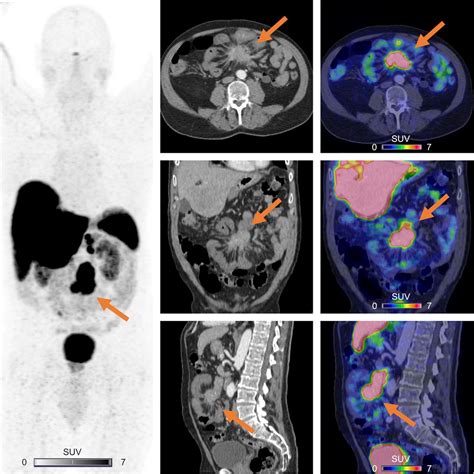

A Dotatate PET scan—often formally referred to as a Gallium-68 (Ga-68) DOTATATE PET/CT scan—is a sophisticated type of molecular imaging. Unlike conventional scans like CT or MRI, which primarily look at the size and shape of body structures, a PET scan focuses on how cells function at a molecular level.

The "Dotatate" component is a radioactive pharmaceutical agent. It acts as a targeted seeking device that binds to somatostatin receptors. These receptors are often found in high concentrations on the surface of neuroendocrine tumor cells. Because these tumors "light up" when the tracer binds to them, the PET scan creates a vivid map of where these tumors are located throughout the body, even those that are too small to be detected by standard imaging.

Interpreting the Results

Once the scan is complete, the images are sent to a radiologist or nuclear medicine physician who specializes in interpreting these complex studies. They will analyze the images to identify areas of high tracer uptake, which indicate the presence of neuroendocrine tumor cells. The results are typically combined with findings from other tests and your clinical history to provide a comprehensive summary of your condition.